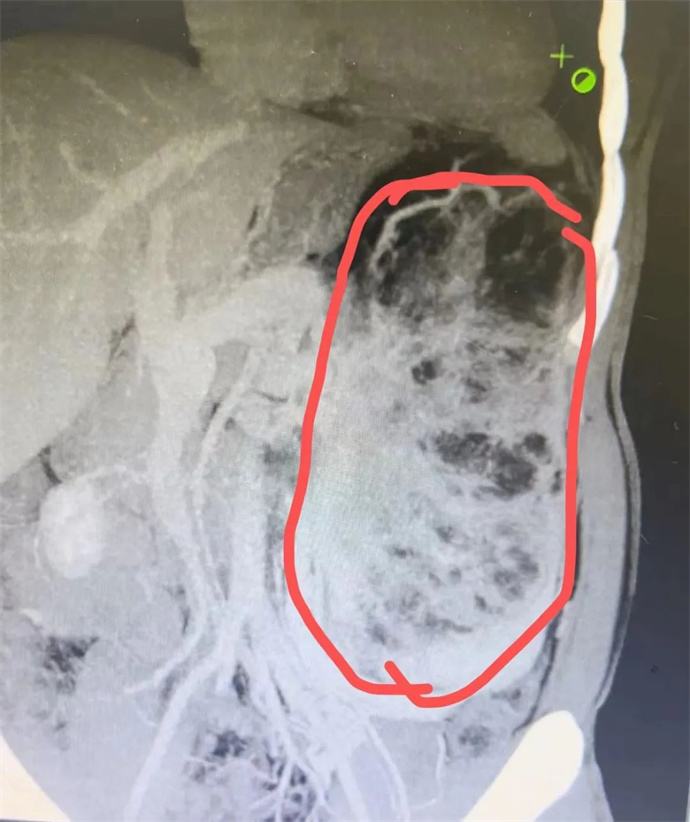

近日,我院泌尿外科會診一位四十多歲男性患者時發現,該患者腹部有一巨大腫瘤,直徑近30cm,已將該患者胃、胰腺、脾臟及部分腸管擠壓移位,且腫瘤內可見大量動靜脈畸形,存在極大的出血風險,一旦出血將危及患者生命,客觀告知患者及家屬相關病情后,患者及家屬憂心忡忡,基本的日常活動都心有畏懼,充分溝通后,轉入泌尿外科,擬行手術治療。

轉入泌尿外科后,強永春主任及專家組積極術前準備,仔細閱片,充分討論,明確此腫瘤來源為左側腎臟,多考慮為腎臟血管平滑肌脂肪瘤,俗稱“錯構瘤”。周莉護士長帶領護理組通過傾聽、解釋、鼓勵、提供支持、建立信任等來安撫患者的憂心忡忡,幫助他們更好地應對疾病。科學、客觀的指導患者的術后康復。

強永春主任帶領泌尿外科團隊積極協調,提前預約腫瘤介入王忠主任,于術前行介入栓塞,減少術中出血風險;同時聯系輸血科提前術中備血;因腫瘤已侵及腎臟大部及腎臟血管,無法保留腎單位行腎部分切除,故先側臥位行后腹腔鏡下微創手術,游離并處理腎臟血管,確保切除時安全,再仰臥位行錯構瘤及腎臟切除;充分準備后,手術按預定方案如期進行,歷時6小時,成功拆除“定時炸彈”。目前患者已出院恢復了日常工作。